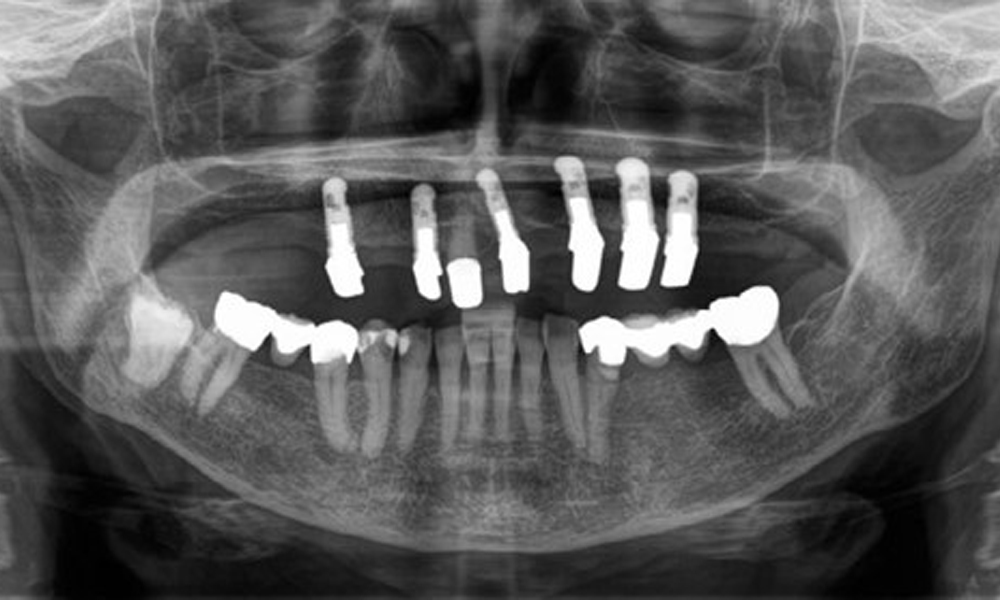

The radiological findings show partially edentulous dentition with maxillary implants for teeth 15, 13, 21, 23, 24, 25 and a telescopic crown on tooth 11. Adequate mandibular bridges spanning 37 to 34 and 45 to 47 are present. 48 is impacted. There are suspected secondary caries distally on 43 and mesially on 44. 44 is restored with a non-radiopaque cavity lining. There is generalised horizontal bone loss of approx. 10% to 30% and localised vertical bone loss affecting teeth 22 and 42 (Fig. 5).

Panoramic X-ray image. The patient has a full set of adult teeth with generalised bone loss of between 10% and 30%. There is radiological suspicion of secondary caries on 44 and 43.

Fig. 5: Panoramic X-ray image. The patient has a full set of adult teeth with generalised bone loss of between 10% and 30%. There is radiological suspicion of secondary caries on 44 and 43.